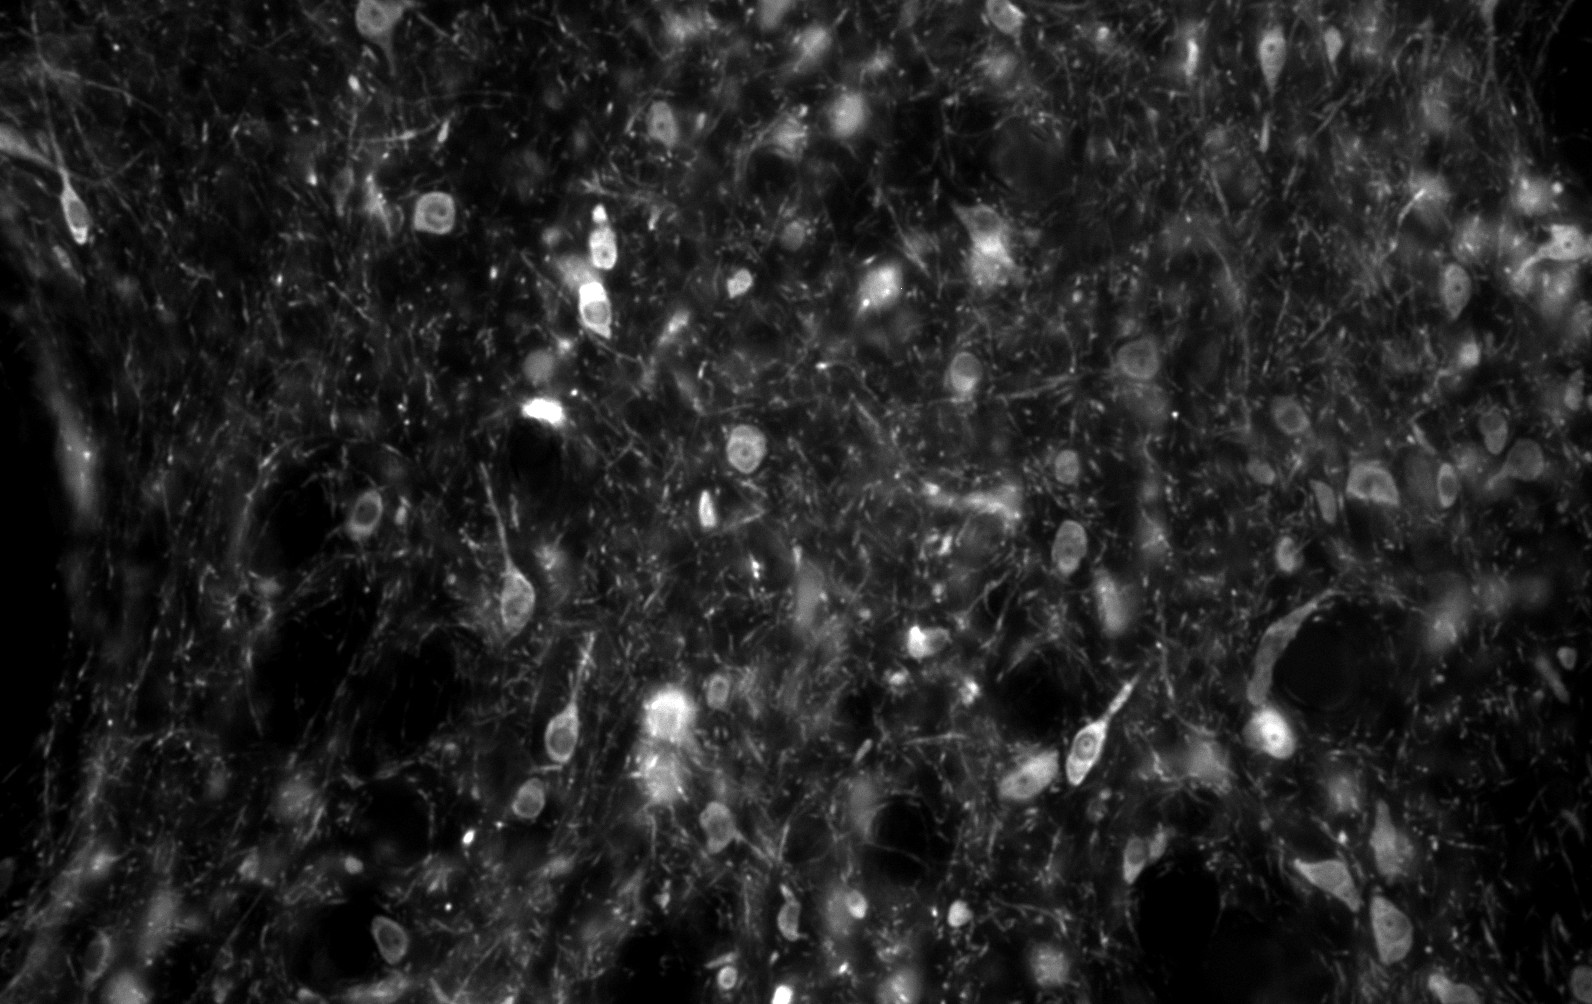

At the center of the circuits we study are the ventral tegmental area (VTA) and the lateral habenula (LHb). The VTA is the source of dopamine in the reward circuitry of the brain. We are investigating how they change in disease states and following drugs of abuse and/or stress, with the goal of identifying a target for a treatment for alcoholism and addiction. We also complete pharmacological ex vivo screening to probe the heterogeneity of VTA neurons and conduct detailed anatomical and morphological analyses of the circuits and neurons of this brain region. The VTA neurons are rich in neuropeptide receptors, especially opioid receptors, enabling us to utilize acute brain slices to differentiate GPCR pharmacologies that have been difficult to detect in heterologous systems. This method of testing compound pharmacology in real brain tissue at the single neuron, physiological level, gives us the opportunity to more accurately predict in vivo activity at the behavioral level than heterologous systems. Together, this ongoing research informs our understanding of the normal and compromised function of the motivational circuits through the VTA and LHb, with the goal of identifying new molecular targets for therapeutically modulating these circuits.